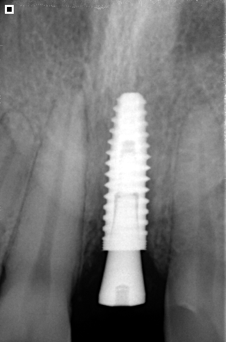

- Implante fabricado en Titanio Grado V de la más alta pureza.

- Reemplaza la raíz del diente y evita la perdida de hueso.

- Indicado para adultos y tercera edad.

- Respaldo casa de implantes SIN